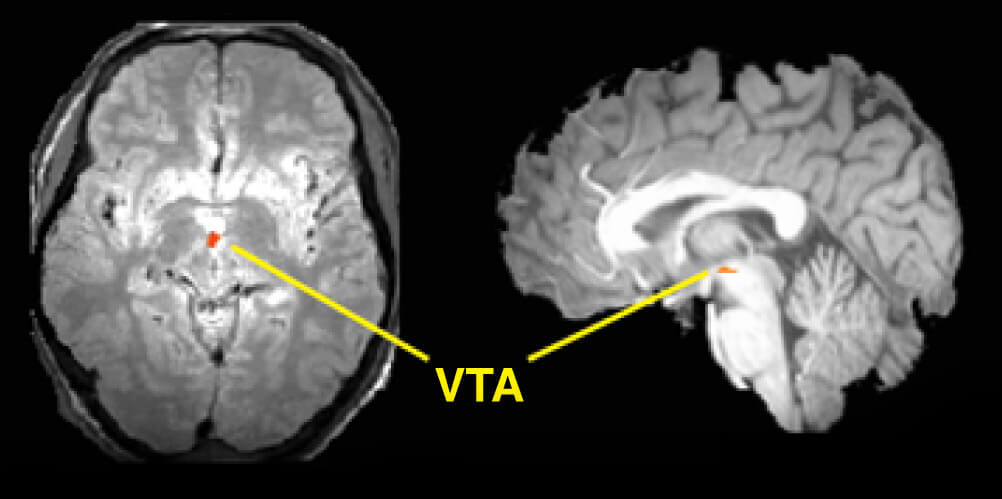

Toen Dr. Fisher koppels middels een fMRI scan (een scan die een gedetailleerd beeld geeft van welke hersendelen het meest actief zijn) onderzocht, vond zij dat wanneer wij verliefd zijn een systeem dat diep in ons brein ligt actief wordt. Dit systeem heet het ventrale tegmentum (VTA), en is verbonden aan motivatie, focus en verlangen. Het laat stoffen als dopamine vrij, die ons een gevoel van beloning geven. Waarschijnlijk heb je het nu al geraden: hetzelfde systeem wordt actief wanneer we blootgesteld worden aan drugs zoals cocaïne. Het verschil is echter dat bij cocaïne het effect weer afneemt, maar bij een romantische relatie blijft het in je hoofd en gaat het niet meer weg. Het is als een obsessie.